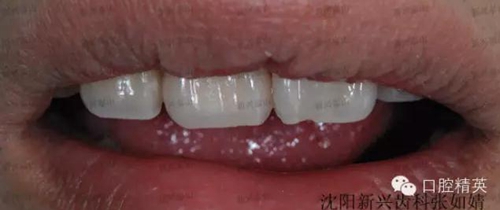

這是一個月前就診的患者,右上中切牙唇側(cè)牙齦有一個大膿包。在照片上可以看到烤瓷牙非常不美觀,一眼就能看出是假的,在前牙的位置,非常明顯,兩牙間還有很大的縫隙,顯得人比較呆板。

看看最后的成果吧。

怎么樣,真的是一次真實的蛻變吧!

牙齒在制作時花了點心思,既關閉了前牙縫隙,又沒有使這顆牙變得很大,患者非常滿意,很高興。

對比一下前后,視覺沖擊一下吧。

照片角度拍攝有些不一樣,但是變化還是非常明顯的。,右上中切牙唇側(cè)膿包還有點印跡,因個體的差異,慢慢會完全吸收,需要時間。

這是一顆鑄瓷牙,內(nèi)冠沒有金屬,消除了金屬對身體的刺激、對牙齦的刺激。金屬對牙齦刺激可能導致牙齦緣的變色即牙齦黑線,刺激牙齦退縮,對牙周易引起加重病變?,F(xiàn)在非金屬的牙冠越來越受到大家的認可,全瓷冠擁有足夠的強度,既美觀又健康。鑄瓷不是最好的全瓷冠,依據(jù)患者的經(jīng)濟情況及牙齒情況,推薦鑄瓷牙,有很高的透光度,接近牙齒,美觀性很高,這是最好最適合患者的選擇。